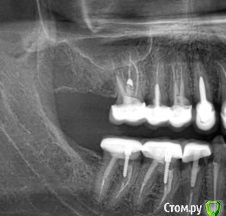

МартаМ Опубликовано 3 августа, 2017 Поделиться Опубликовано 3 августа, 2017 Добрый день. Буду очень благодарна за консультацию.Правая нижняя шестерка начала болеть в прошлом декабре. Боль ощущалась при нажатии, постукивании именно в этом зубе.Врач отправила на панорамный снимок,оказалась киста между пятым и шестым. Пятый удалили, кисту вычистили. Шестерка продолжает болеть.Несколько дней назад сделала еще раз снимок. Врач, который делал снимок, сказал, что шестерка справа "проблемная". Моя доктор никакой проблемы не видит.А что вы можете мне по этому поводу сказать?Зуб продолжает болеть, сильная боль при накусывании плюс постоянный дискомфорт где-то в глубине десны. Первый снимок - до удаления пятерки, второй - свежий. Ссылка на комментарий

Doc Опубликовано 5 августа, 2017 Поделиться Опубликовано 5 августа, 2017 В межкорневой зоне явное разрежение. Либо бифуркация, либо перфорация. И то и другое - повод для удаления. Но по одному снимку диагноз нельзя ставить и тем более удалять зуб. 1 Ссылка на комментарий

Павел7809 Опубликовано 7 августа, 2017 Поделиться Опубликовано 7 августа, 2017 Судя по снимку - зубу конец. И есть сомнения по поводу следующего. Ссылка на комментарий

МартаМ Опубликовано 10 августа, 2017 Автор Поделиться Опубликовано 10 августа, 2017 В межкорневой зоне явное разрежение. Либо бифуркация, либо перфорация. И то и другое - повод для удаления. Но по одному снимку диагноз нельзя ставить и тем более удалять зуб.Врач уверяет, что затемнение вызвано тем, что зуб разрушен глубоко под десну, а боль - невралгия. У невролога была, проблем не обнаружили. Ссылка на комментарий

Doc Опубликовано 10 августа, 2017 Поделиться Опубликовано 10 августа, 2017 Врач уверяет, что затемнение вызвано тем, что зуб разрушен глубоко под десну, а боль - невралгия. У невролога была, проблем не обнаружили.Собственно, если зуб разрушен глубоко под десну, то именно это и есть показание к удалению, а невралгия тут не причем. 1 Ссылка на комментарий

dok1 Опубликовано 11 августа, 2017 Поделиться Опубликовано 11 августа, 2017 Да там и 44 внимания требует. Ссылка на комментарий